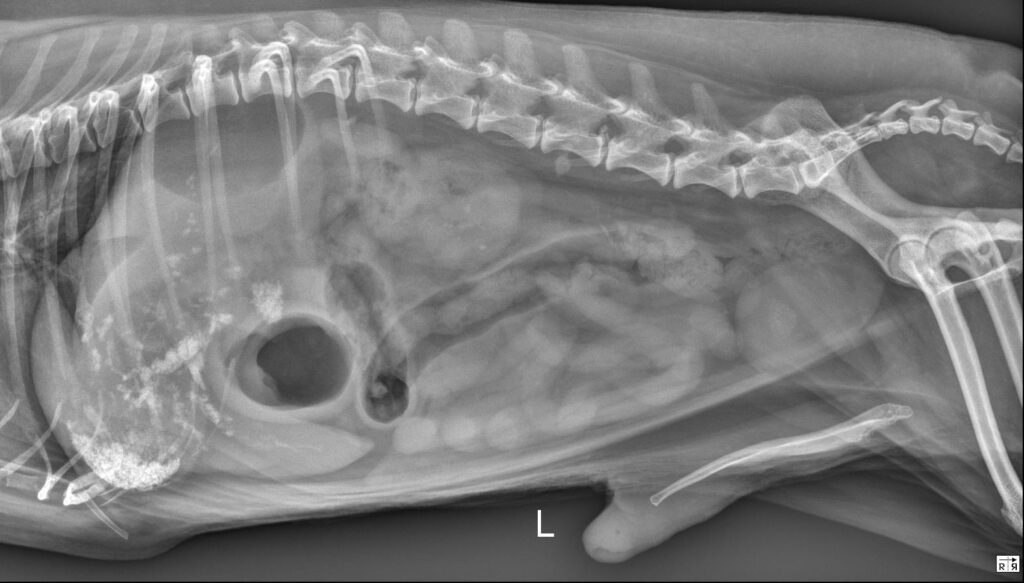

Radiology Quiz March 2026

History 5 year old male castrated cat. Has been treated for elevated renal values.

...